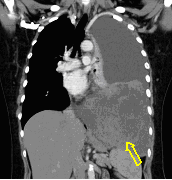

Image

6. c

6. d

64 year old man. Infiltration and abscess development in the right lower lobe.

c.) CT lung window, coronal reformat, d.) axial, mediastinal window. Extensive area in the right 8-9th segments without air, including many associated lesions of fluid density, with tiny air bubbles, larger air spaces and air-fluid level. The lesion has almost a triangular shape, its dorsal and ventral contours are arched, its peak points towards the lower pole of the hilum.